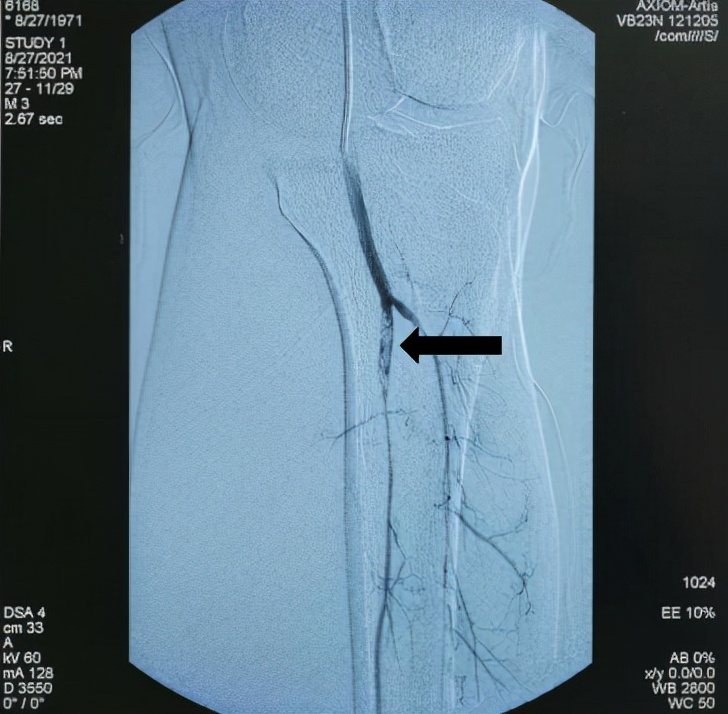

术中造影提示血栓栓塞处